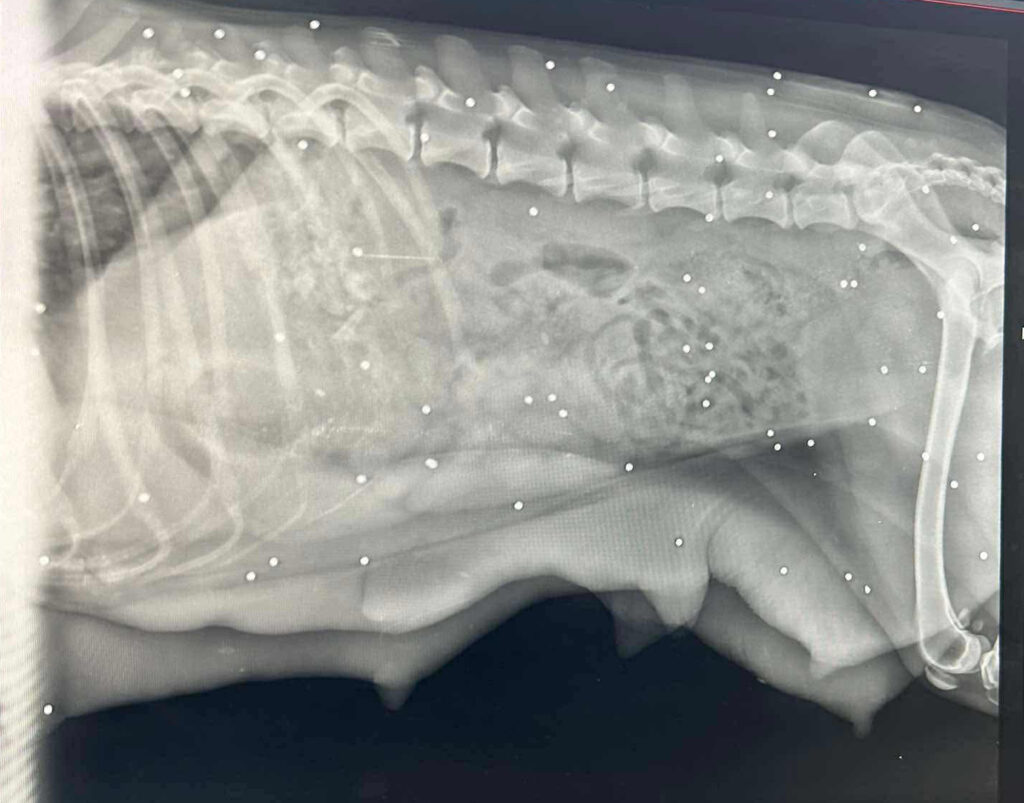

Bemerkungen: Auf die Hündin wurde wohl geschossen. Sie ist geröngt, allerdings steht das medizinische Gutachten noch aus.

Als diese Junghündin hier im Tierheim einziehen durfte, da war das eine sehr gute Sache, denn auf sie wurde geschossen!